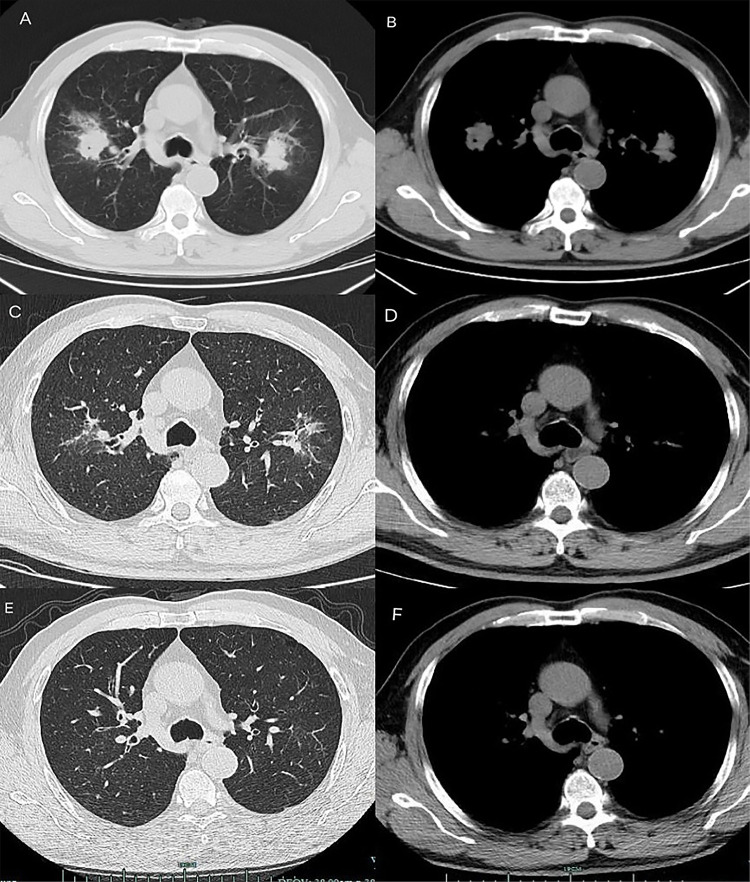

Results: All patients had oral diseases, and 75% were long-term smokers. The primary clinical manifestations were nonspecific respiratory symptoms, including cough, fever, chest pain, and hemoptysis. Chest CT revealed consolidation and cavitation in the upper lobes of the lungs. T. forsythia was successfully detected by mNGS of BALF, while conventional cultures failed to identify pathogens in all cases. All patients received combination antibiotic therapy based on metronidazole and piperacillin-tazobactam, with some cases requiring additional antibiotics. Following treatment, significant clinical improvement was observed, and follow-up imaging demonstrated gradual resolution of the lesions.